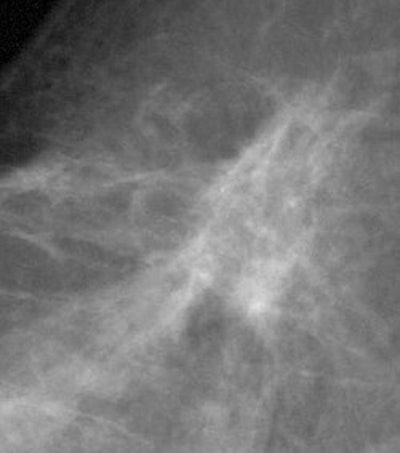

![]() ![]() |

DSPM images acquired on the Mammomat 3000 Nova, including zoom (middle) and spot magnification (below). Images courtesy of Dr. Wolfgang Matzek.

![]() |